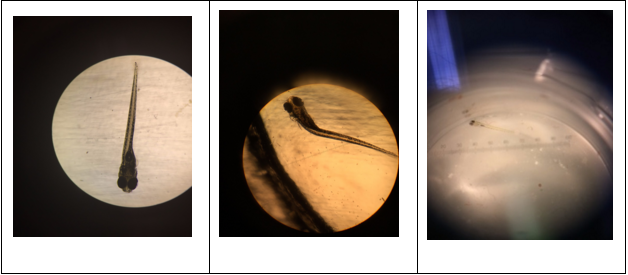

Developmental Stages Seen in Zebrafish Figure 38-40. Different developmental stages of the zebrafish seen under a dissecting microscope. Fig. 38 shows the 13 somite stage, fig. 39 shows the 48 hour stage, and fig. 40 shows a fully developed zebrafish.

Abnormalities: Shape Figure 41-44. Abnormalities in zebrafish shape, specifically with respect to curvature of body seen under dissecting scope (fig. 41,42) and under compound microscope at 4x (fig. 43,44). Fig. 41 and 43 have no abnormalities and serve as comparisons for fig. 42 and 44, where body is deformed.

Abnormalities: Fin Development and Swimming Abilities Figure 52-54. Abnormalities seen in fin development and swimming abilities of the fish under a compound microscope at 4x (fig. 52-53) and a dissecting microscope (fig. 54). Fig. 52 shows normal fin development and fig. 53-54 show abnormal fins leading to difficulty swimming and decreased motility. Fig. 53 shows a normal fin on the left side and an anomalous right fin that can not be seen due to its small size or lack thereof. Fig. 54 shows a fish that did not develop any fins and as a result, is seen floating on its right side, unable to swim.